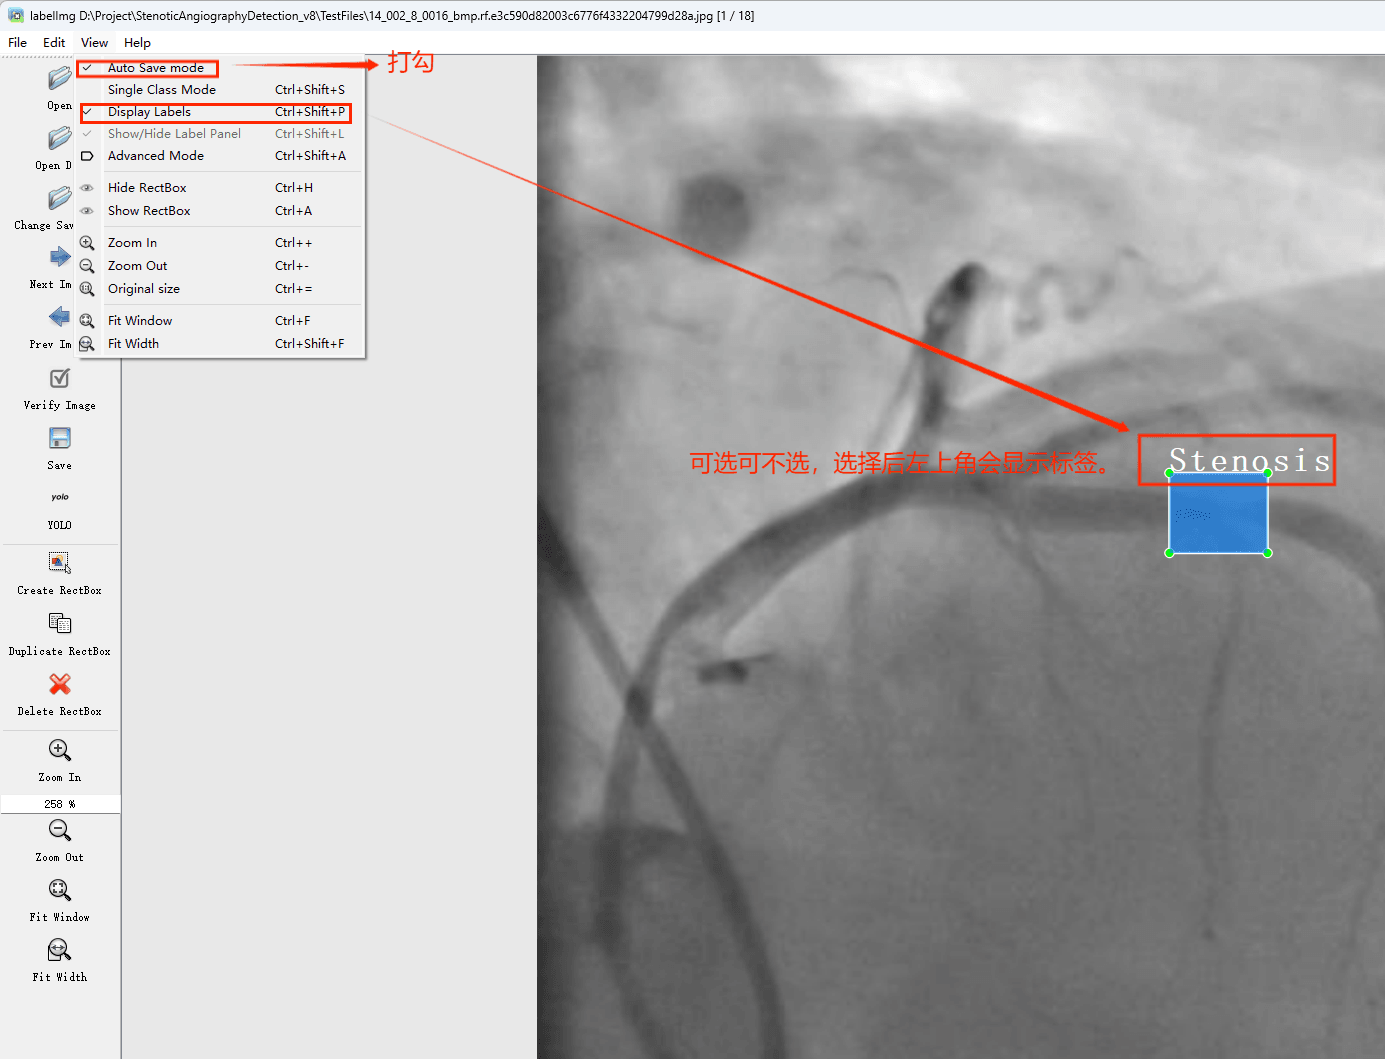

初识labelimg

打开后,我们自己设置一下

在View中勾选Auto Save mode

接下来我们打开需要标注的图片文件夹

并设置标注文件保存的目录(上图中的Change Save Dir)

接下来就开始标注,画框,标记目标的label,然后d切换到下一张继续标注,不断重复重复。